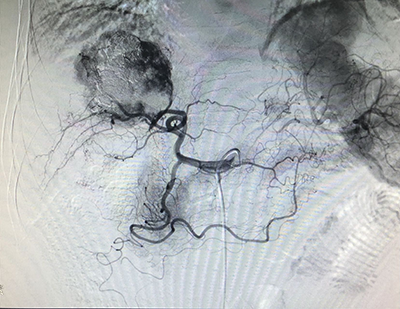

![]() | ![]() |

| (肝癌的粒子植入治疗) | (肺癌的粒子植入治疗) |